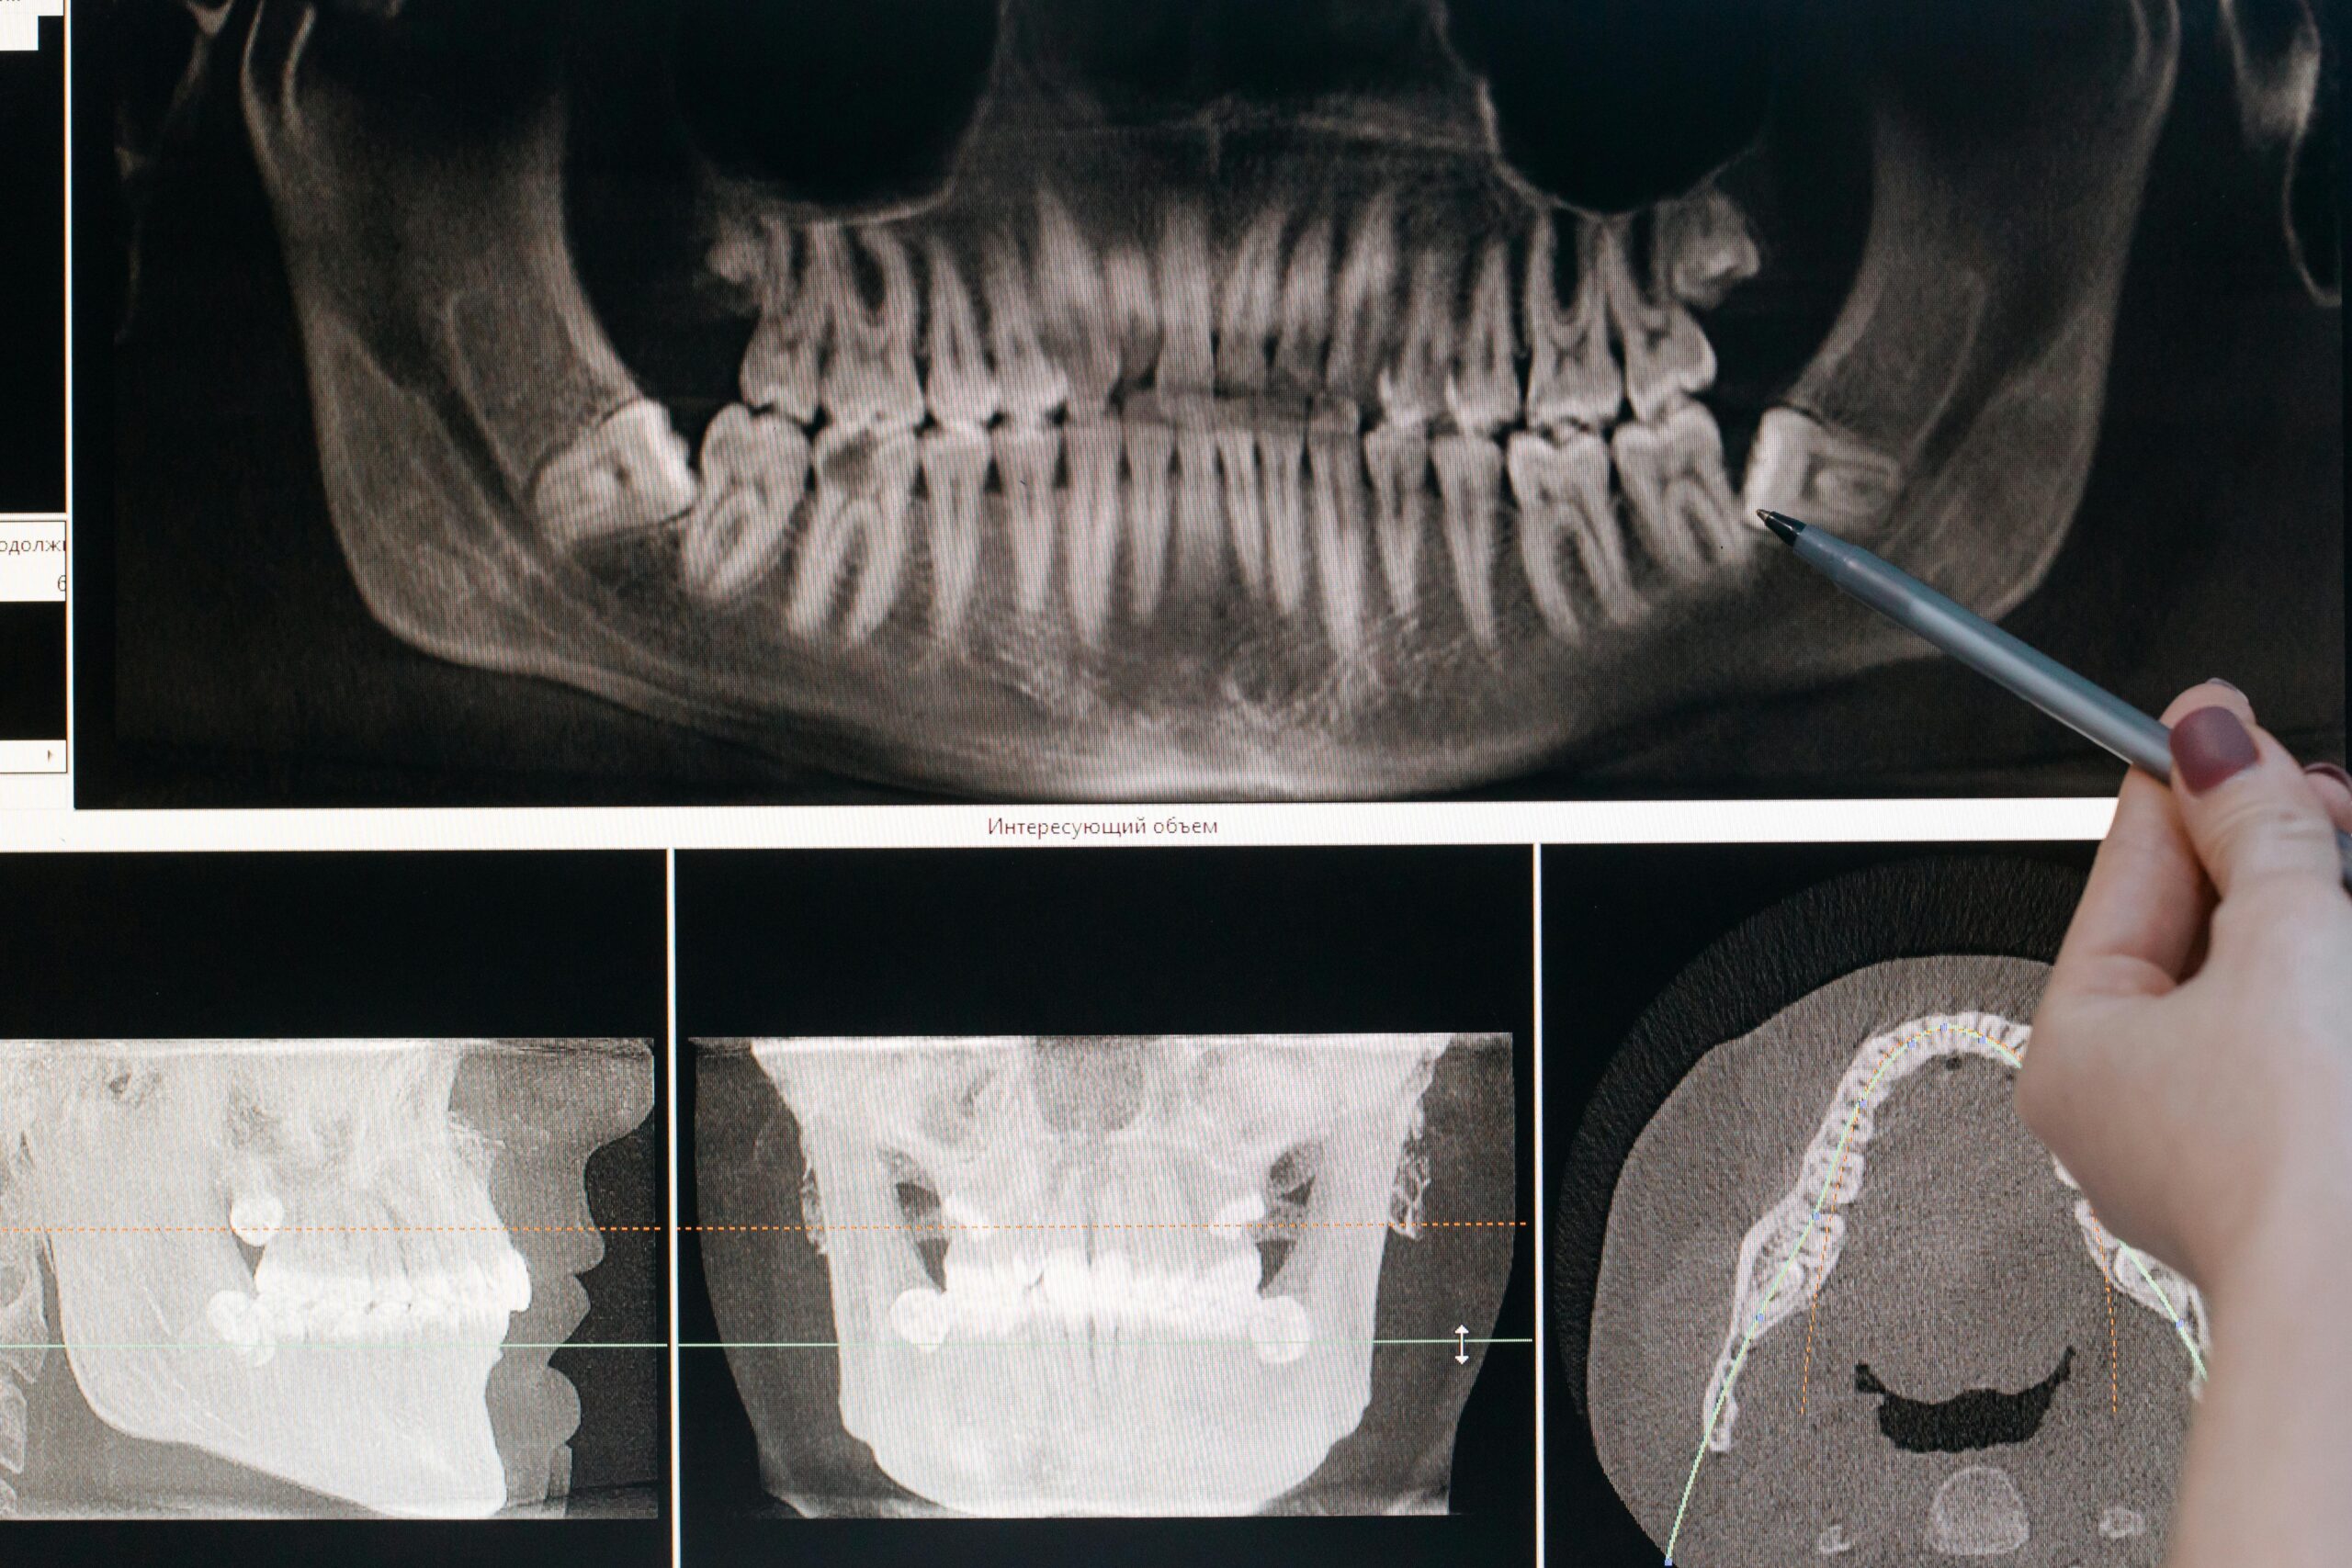

Velocidad y calidad en los estudios

Proceso digitalizado y en tiempo real